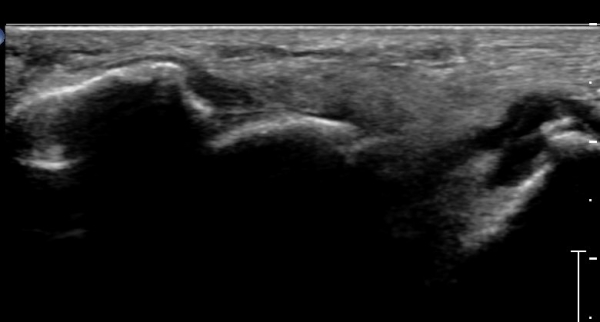

Á¾°ñÀÔ¹æ°ñ°üÀý Á¾´Ü¸é°Ë»ç»ó Á¾°ñ Àü¹æµ¹±â °ß¿­°ñÀý°ú Á¦4ÁßÁ·°ñ °ß¿­°ñÀýÀÌ °üÂûµÈ´Ù(»çÁø 2).

Á¾°ñ Àü¹æµ¹±â Ⱦ´Ü¸é°Ë»ç»ó Àü¹æµ¹±â ¿ÜÃø°ú ³»ÃøºÎ °ß¿­°ñÀýÀÌ °üÂûµÈ´Ù(»çÁø 3).